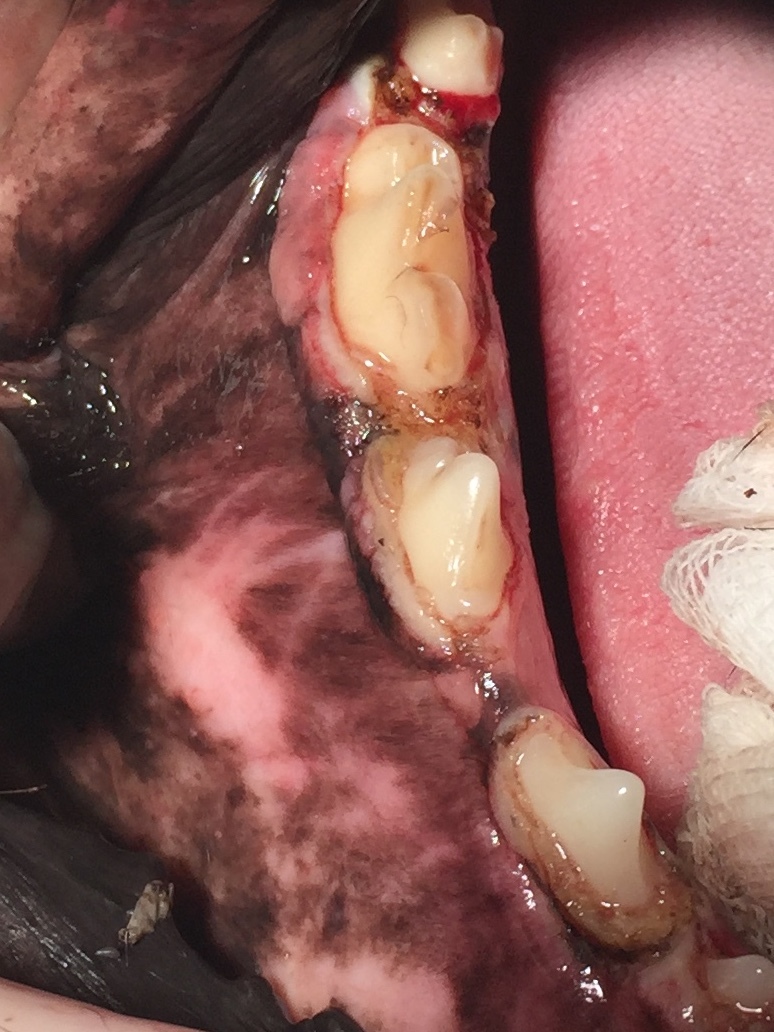

Dann sahen wir uns die Maulhöhle an, in der wir insgesamt 24 Lokalisationen am Zahnfleisch markieren konnten, die behandlungsbedürftig waren. (Abb. 1-4). Das Zahnfleisch wies sogenannte periphere odontogene Fibrome auf, die umgangssprachlich auch als Epuliden bezeichnet werden. Der Boxer, die Bordeaux Dogge, der Mops und die Französiche Bulldogge weisen hier eine Prädisposition auf, haben also eine Veranlagung zur Ausbildung dieser Tumore.

Von der Einteilung bezeichnet man die Epuliden als gutartige Zubildungen, die dem Zahnfleisch aufsitzen. Sie bilden keine Metastasen (Tochtergeschwülste) aus. Allerdings können sie erhebliche Ausmaße annehmen, wie man anhand der Abb.3 sehen kann. Die Epuliden können somit sowohl zu einer mechanischen Einschränkung beim Zermahlen des Futters als auch zu entzündlichen Veränderungen führen, dadurch erhebliche Schmerzen verursachen und sogar Zähne verdrängen. Zusätzlich konnte man in allen vier Quadranten bei Inspektor eine Gingivahyperplasie verzeichnen, die sich durch überwuchernde Zahnfleischbereiche darstellt. Teilweise werden ganze Zähne überwachsen vom Zahnfleisch, so dass hier massive Taschen entstehen, die Futterreste, Haare und anderes Fremdmaterial aufnehmen (Abb 1). Die daraus folgenden Entzündungen, die sich bis auf den tieferen Zahnhalteapparat auswirken, bedingen einen Rückgang des Knochens. Die Parodontitis ist in vollem Gange und lässt sich nur noch stoppen, aber nicht mehr heilen. Betroffene Zähne werden ab einem Furkationsbefall Grad 3 (die Wurzelaufteilung liegt gut sondierbar frei) extrahiert.